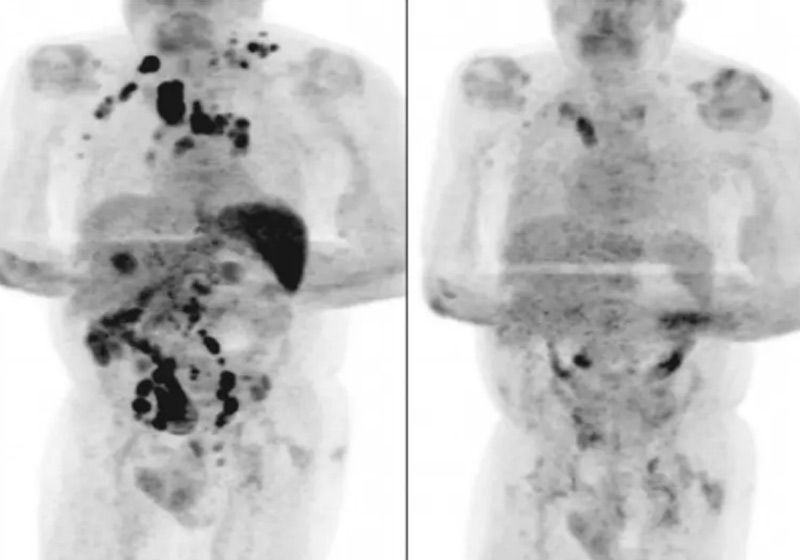

Quatro meses depois, os médicos afirmaram que o inchaço dos nódulos havia diminuído.

Um exame de tomografia revelou a remissão generalizada do linfoma.

A hipótese levantada pelos autores do artigo é de que a infecção pelo novo coronavírus desencadeou uma resposta imune contra o tumor.